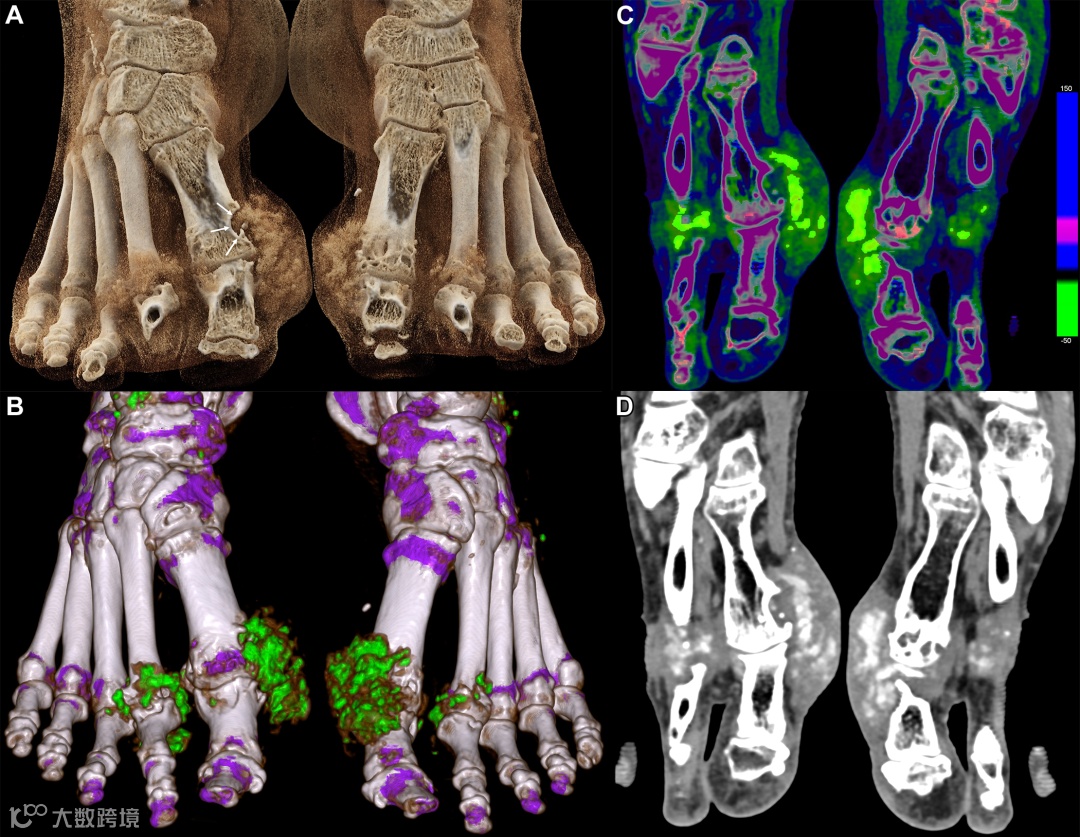

图1. 痛风患者的 photon-counting CT 图像(Naeotom Alpha,西门子医疗)

(A)使用厂商提供的后处理软件重建的体积重建影像显示,第一和第二跖趾关节周围的痛风结节。痛风结节对骨的侵蚀影响在右侧第一跖趾关节(箭头)尤为明显。

(B)尿酸沉积映射显示两只脚的总尿酸体积为12.4 cm³。

(C)轴位有效原子序数(Zeff)彩色图谱展示了痛风结节的结构组织,其中尿酸晶体(浅绿色)嵌入在纤维组织中。

(D)与C 图相同水平的轴位灰度图像显示,痛风结节在第一和第二跖趾关节中的异质性。

A图的影像参数如下:层厚0.2 mm;视野270 × 270 mm;矩阵大小1024 × 1024;重建核函数Br84(锐核);量子迭代重建QIR-2。

B图和C图(光谱图像)及D图(软组织图像)的重建参数如下:层厚0.8 mm;视野270 × 270 mm;矩阵大小512 × 512;重建核函数Br40;量子迭代重建QIR-2。